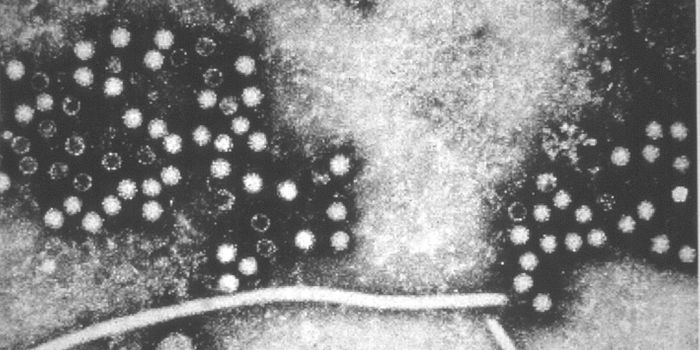

AUG 05, 2017

Microbiology

There are several kinds of hepatitis, and while types A, B, and C get attention, hepatitis E (HEV) is becoming more prev

...

Written By:

Carmen Leitch